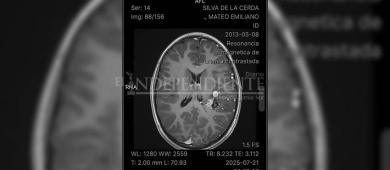

San José del Cabo, Baja California Sur.- Mateo de solo 12 años de edad es un niño originario de San José del Cabo (SJC), quien recientemente fue diagnosticado con una malformación cerebral. La familia solicita el apoyo de la población para solventar sus gastos.

A través de la plataforma de donativos Gofundme.com la familia de Mateo brindó más detalles al respecto de su estado de salud. El diagnostico oficial es "malformación arteriovenosa grado IV".

Esta malformación se localiza en la parte izquierda de su cerebro, lo cual genera un "nido vascular". Este padecimiento es difícil de tratar por el aumento de irrigación sanguínea por las venas y arterias que se alojan en esta parte de su cerebro.